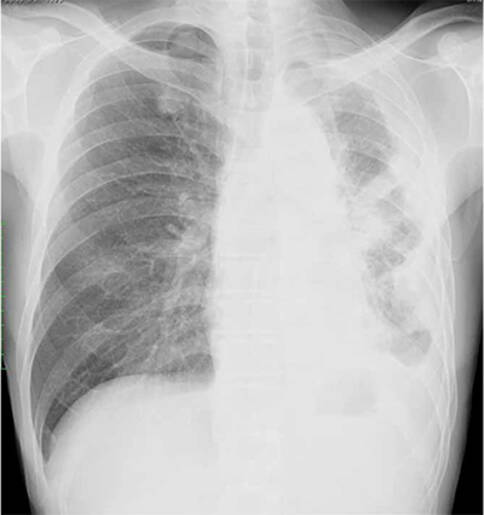

90%以上的间皮瘤病人都有胸膜病变(其他10%病人表现为心包间皮瘤和腹膜间皮瘤),X线胸片表现为单侧或双侧弥散性胸膜增厚,常致肋膈角变钝。胸腔积液存在于95%的病例,并且通常为单侧性,量多,为血性。诊断依据胸水细胞学或胸膜活检。胸水透明质酸酶水平升高提示有但不能诊断间皮▪瘤。如果以上无法确诊,则通过胸腔镜或开胸活检完成。研究发现由间皮细胞产生释放入血的可溶性间皮素相关蛋白可能作为肿瘤标志物用于疾病的诊断和监测,但假阳性率可能会限制其价值。

胸膜间皮瘤影像,图源:日本呼吸学会